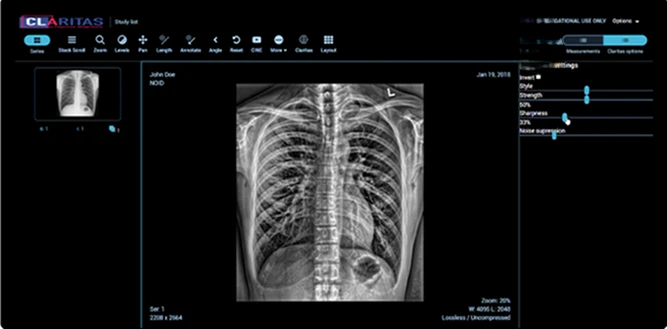

Tecnologia de ponta para aprimoramento de imagens radiológicas

O iRAD é um produto de software de última geração baseado em nosso algoritmo inovador que fornece aprimoramento ideal para imagens de radiologia. O iRAD oferece aos clínicos uma ferramenta poderosa, mas simples de usar, baseada na nuvem, que se integra perfeitamente ao fluxo de trabalho existente.

O iRAD aprimora imagens para revelar características difíceis de ver, melhorando contraste, nitidez e realce de bordas

Integração simples e rápida com sistemas existentes

Mantém o fluxo de trabalho existente inalterado

Suporte para múltiplas modalidades de imagem

Compatível com todos os tipos de arquivo de imagem